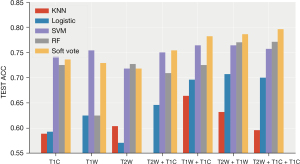

- Plan A (I + II): (see Table 2, Figure 6)

The prediction performances of all models in plan A (95% confidence interval)Model Performance T2W T2W + T1C T1W + T1C T2W + T1W T2W + T1W + T1C Logistic ACC 0.586 (0.536, 0.636) 0.691 (0.648, 0.734) 0.646 (0.615, 0.678) 0.764 (0.72, 0.809) 0.725 (0.693, 0.757) AUC 0.61 (0.538, 0.681) 0.682 (0.639, 0.726) 0.657 (0.585, 0.73) 0.784 (0.735, 0.834) 0.752 (0.703, 0.8) KNN ACC 0.554 (0.476, 0.631) 0.588 (0.532, 0.644 0.593 (0.569, 0.616) 0.718 (0.663, 0.773) 0.693 (0.644, 0.742) AUC 0.569 (0.48, 0.658) 0.646 (0.595, 0.698) 0.552 (0.506, 0.599) 0.683 (0.613, 0.752) 0.662 (0.604, 0.72) SVM ACC 0.729 (0.674, 0.784) 0.606 (0.519, 0.693) 0.768 (0.723, 0.812) 0.743 (0.713, 0.773) 0.775 (0.745, 0.805) AUC 0.606 (0.506, 0.706) 0.739 (0.7, 0.779) 0.652 (0.594, 0.71) 0.757 (0.697, 0.818) 0.754 (0.678, 0.83) RF ACC 0.714 (0.669, 0.76) 0.716 (0.668, 0.765) 0.736 (0.687, 0.784) 0.777 (0.738, 0.815) 0.761 (0.735, 0.786) AUC 0.654 (0.586, 0.722) 0.77 (0.738, 0.801) 0.722 (0.665, 0.78) 0.808 (0.769, 0.848) 0.74 (0.687, 0.793) Vote ACC 0.743 (0.705, 0.78) 0.697 (0.632, 0.761) 0.771 (0.727, 0.816) 0.768 (0.742, 0.794) 0.775 (0.755, 0.795) AUC 0.66 (0.586, 0.734) 0.761 (0.724, 0.797) 0.712 (0.65, 0.775) 0.804 (0.773, 0.836) 0.752 (0.7, 0.803) ACC, accuracy; AUC, area under curve.

RF showed the best performance, reaching the highest average accuracy rate of 0.777 (0.738, 0.815) and AUC of 0.808 (0.769, 0.848) on the T2W + T1W sequence. The performance of the classification model and SVM after the integration of the two strong classifiers was slightly lower than that of the RF, and both reached the highest average accuracy on the T2W + T1W + T1WC sequence: ACC: 0.775 (0.755, 0.795), AUC: 0.752 (0.7, 0.803) and ACC: 0.775 (0.745, 0.805) AUC: 0.754 (0.687, 0.83). Compared to the other sequences, the T2W sequence had better effects on different classifications.

- Plan B (I + III): (see Table 3, Figure 7)

The prediction performances of all models in plan B (95% confidence interval)Model Performance T2W T2W + T1C T1W + T1C T2W + T1W T2W + T1W + T1C Logistic ACC 0.571 (0.509, 0.634) 0.654 (0.608, 0.699) 0.668 (0.619, 0.716) 0.707 (0.658, 0.757) 0.711 (0.672, 0.749) AUC 0.576 (0.501, 0.65) 0.671 (0.596, 0.747) 0.684 (0.629, 0.738) 0.756 (0.709, 0.804) 0.713 (0.648, 0.778) KNN ACC 0.6 (0.538, 0.662) 0.557 (0.506, 0.608) 0.65 (0.591, 0.709) 0.607 (0.561, 0.653) 0.582 (0.518, 0.646) AUC 0.58 (0.515, 0.644) 0.543 (0.479, 0.606) 0.581 (0.509, 0.652) 0.605 (0.552, 0.657) 0.574 (0.496, 0.652) RF ACC 0.732 (0.699, 0.765) 0.705 (0.659, 0.752) 0.748 (0.721, 0.776) 0.782 (0.741, 0.823) 0.773 (0.718, 0.828) AUC 0.642 (0.583, 0.702) 0.62 (0.567, 0.672) 0.654 (0.577, 0.731) 0.733 (0.667, 0.799) 0.668 (0.59, 0.746) Vote ACC 0.732 (0.709, 0.756) 0.757 (0.721, 0.793) 0.786 (0.766, 0.806) 0.786 (0.758, 0.814) 0.789 (0.763, 0.816) AUC 0.639 (0.585, 0.692) 0.61 (0.554, 0.665) 0.649 (0.57, 0.728) 0.717 (0.657, 0.777) 0.659 (0.583, 0.735) ACC, accuracy; AUC, area under curve.

The classification model integrated by two strong classifiers showed the best performance, reaching the highest average accuracy rate of 0.789 (0.763, 0.816) and AUC of 0.659 (0.583, 0.735) on the T2W + T1W + T1WC sequence. Performance was relatively stable, and the accuracy rate was higher than 70% in the seven sequence combinations. Following a RF, the average accuracy rate reached 0.782 (0.741, 0.823), and the AUC reached 0.733 (0.667, 0.799) in the T2W + T1W sequence. The results of the nearest neighbor and logistic regression models are not ideal, especially the nearest neighbor algorithm.

- Plan C (I + II + III): (see Table 4, Figure 8)

The prediction performances of all models in plan C (95% confidence interval)Model Performance T2W T2W + T1C T1W + T1C T2W + T1W T2W + T1W + T1C Logistic ACC 0.593 (0.528, 0.658) 0.646 (0.602, 0.691) 0.696 (0.633, 0.76) 0.707 (0.666, 0.748) 0.7 (0.664, 0.736) AUC 0.576 (0.512, 0.641) 0.671 (0.607, 0.735) 0.681 (0.636, 0.726) 0.737 (0.677, 0.798) 0.731 (0.661, 0.801) KNN ACC 0.589 (0.529, 0.65) 0.532 (0.477, 0.587) 0.664 (0.618, 0.71) 0.632 (0.594, 0.67) 0.596 (0.538, 0.655) AUC 0.56 (0.499, 0.62) 0.544 (0.501, 0.587) 0.624 (0.557, 0.69) 0.612 (0.56, 0.664) 0.579 (0.508, 0.65) RF ACC 0.725 (0.686, 0.764) 0.709 (0.676, 0.742) 0.725 (0.693, 0.757) 0.77 (0.732, 0.807) 0.771 (0.727, 0.816) AUC 0.648 (0.594, 0.703) 0.63 (0.565, 0.695) 0.658 (0.576, 0.74) 0.71 (0.638, 0.782) 0.697 (0.614, 0.78) Vote ACC 0.736 (0.705, 0.766) 0.754 (0.72, 0.787) 0.782 (0.761, 0.803) 0.786 (0.753, 0.818) 0.796 (0.76, 0.833) AUC 0.636 (0.585, 0.688) 0.622 (0.559, 0.686) 0.661 (0.571, 0.75) 0.704 (0.632, 0.777) 0.689 (0.615, 0.763) ACC, accuracy; AUC, area under curve.

After combining the key features of the different sequences, the performance of the three sequences was greatly improved in the integrated classification model [ACC: 0.796 (0.76, 0.833), AUC: 0.689 (0.615, 0.763)]. The average accuracy rate was close to 80%, and the average AUC exceeded 70%. Furthermore, the performance was stable, and the accuracy rate was higher than 70% in multiple sequence combinations.

After the combination of features, the performance of the other models improved to varying degrees. The average accuracy of the RF was 0.771 (0.727, 0.816), and the AUC was 0.697 (0.614, 0.78).

After combining the key characteristics of the different sequences, the combined effect of the three sequences was greatly enhanced in the ensemble model [ACC: 0.796 (0.76, 0.833), AUC: 0.689 (0.615, 0.763)]. The average accuracy rate was close to 80%, and the average AUC exceeded 70% (Figures 9,10).

After analyzing the commonly used classifiers for brain tumors (25,26), we chose five models for classification: logistic regression (logistic), RF, KNN, SVM, and a soft voting integrated model (RF, SVM). The integrated classification model based on RF and SVM had the best predictive performance, which could be due to the combination of the advantages of the two models. In our research, T2W had the highest performance in predicting the expression level of Ki-67 in all sequences, and the acquired image features had a unique degree. The accuracy of the T1W sequence was slightly worse than that of the T2W sequence. In addition, we did not just identify a single sequence to predict the patient’s Ki-67, but also performed seven combinations of three sets of sequences.

We used selected combinations of the most valuable features selected from the different sequences to screen out the more meaningful features to predict Ki-67 expression levels. After the sequences were combined, the prediction performance of the five models was improved to varying degrees. The performance improvement in the logistic regression was particularly obvious. The image features of the different sequences could reflect the expression level of Ki-67, and we could superimpose the features of the different sequences to increase the level of discrimination.

The C plan U-test + RF + LASSO was relatively less used among the three combination schemes in other studies. In our research, the C scheme was more robust and had the highest performance. This finding might be because after adding the linear method (LASSO) and the nonlinear method (RF), the interference of irrelevant variables was eliminated from both angles simultaneously, making its efficiency the highest. This discovery also provided new ideas for subsequent related research.

Although KNN had some improvement after multi-sequence merging, it was still the worst of the models. SVM (RBF) and RF had relatively better effects, and the integrated model was the best. After combining multiple sequences, the effect of logistic regression was greatly improved, indicating that when the key information of the sample was sufficient, some simple linear classification models could also obtain better results.